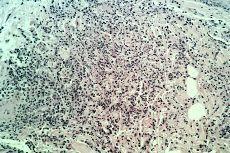

Paciente de 78 años ingresado por ángor pectoris con antecedentes de cardiopatía y vasculopatía periférica isquémicas. Durante su ingreso presentó una erupción cutánea de pápulas y placas congestivas con aspecto vesiculoso, duras a la palpación e intensamente pruriginosas localizadas en cara, cuello y extremidades superiores (Fig. 1). En la exploración física destacaba además una conjuntivitis bilateral y la presencia de aftas bucales. Este cuadro se acompañaba de fiebre de 38° C, leucocitosis (12.000/mm3) con neutrofilia (90%), anemia (Hb 9,6 g/dl), trombopenia (95.000/mm3) y aumento de VSG (79 mm). Además existía una hematuria importante de varios meses de evolución junto a proteinuria y presencia de infiltrados pulmonares persistentes a nivel de lóbulo superior derecho. En la biopsia cutánea se apreció un denso infiltrado de neutrófilos en dermis junto con una gran leucocitoclasia sin daño vascular (Fig. 2). Los cultivos a partir de la biopsia de piel fueron negativos para bacterias, micobacterias y hongos, así como los hemocultivos. Se determinaron los anticuerpos anticitoplasma de neutrófilo (ANCA), siendo negativos. Se realizó el diagnóstico de síndrome de Sweet, desapareciendo rápidamente la erupción tras instaurar tratamiento corticoideo.

FIG. 2.--Infiltrado de neutrófilos en dermis con gran leucocitoclasia.